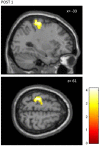

This study examines with transcranial magnetic stimulation (TMS) and with functional magnetic resonance imaging (fMRI) whether 20 min of repetitive peripheral magnetic stimulation (rPMS) has a facilitating effect on associated motor controlling regions. Trains of rPMS with a stimulus intensity of 150% of the motor threshold (MT) were applied over right hand flexor muscles of healthy volunteers. First, with TMS, 10 vs. 25 Hz rPMS was examined and compared to a control group. Single and paired pulse motor evoked potentials (MEPs) from flexor carpi radialis (FCR) and extensor carpi radialis (ECR) muscles were recorded at baseline (T0), post rPMS (T1), 30 min post (T2), 1 h post (T3) and 2 h post rPMS (T4). Then, with fMRI, 25 Hz rPMS was compared to sham stimulation by utilizing a finger tapping activation paradigm. Changes in bloodoxygen level dependent (BOLD) contrast were examined at baseline (PRE), post rPMS (POST1) and 1 h post rPMS (POST2). With TMS facilitation was observed in the target muscle (FCR) following 25 Hz rPMS: MEP recruitment curves (RCs) were increased at T1, T2 and T3, and intracortical facilitation (ICF) was increased at T1 and T2. No effects were observed following 10 Hz rPMS. With fMRI the BOLD contrast at the left sensorimotor area was increased at POST1. Compared to inductions protocols based on transcutaneous electrical stimulation and mechanical stimulation, the rPMS induced effects appeared shorter lasting.